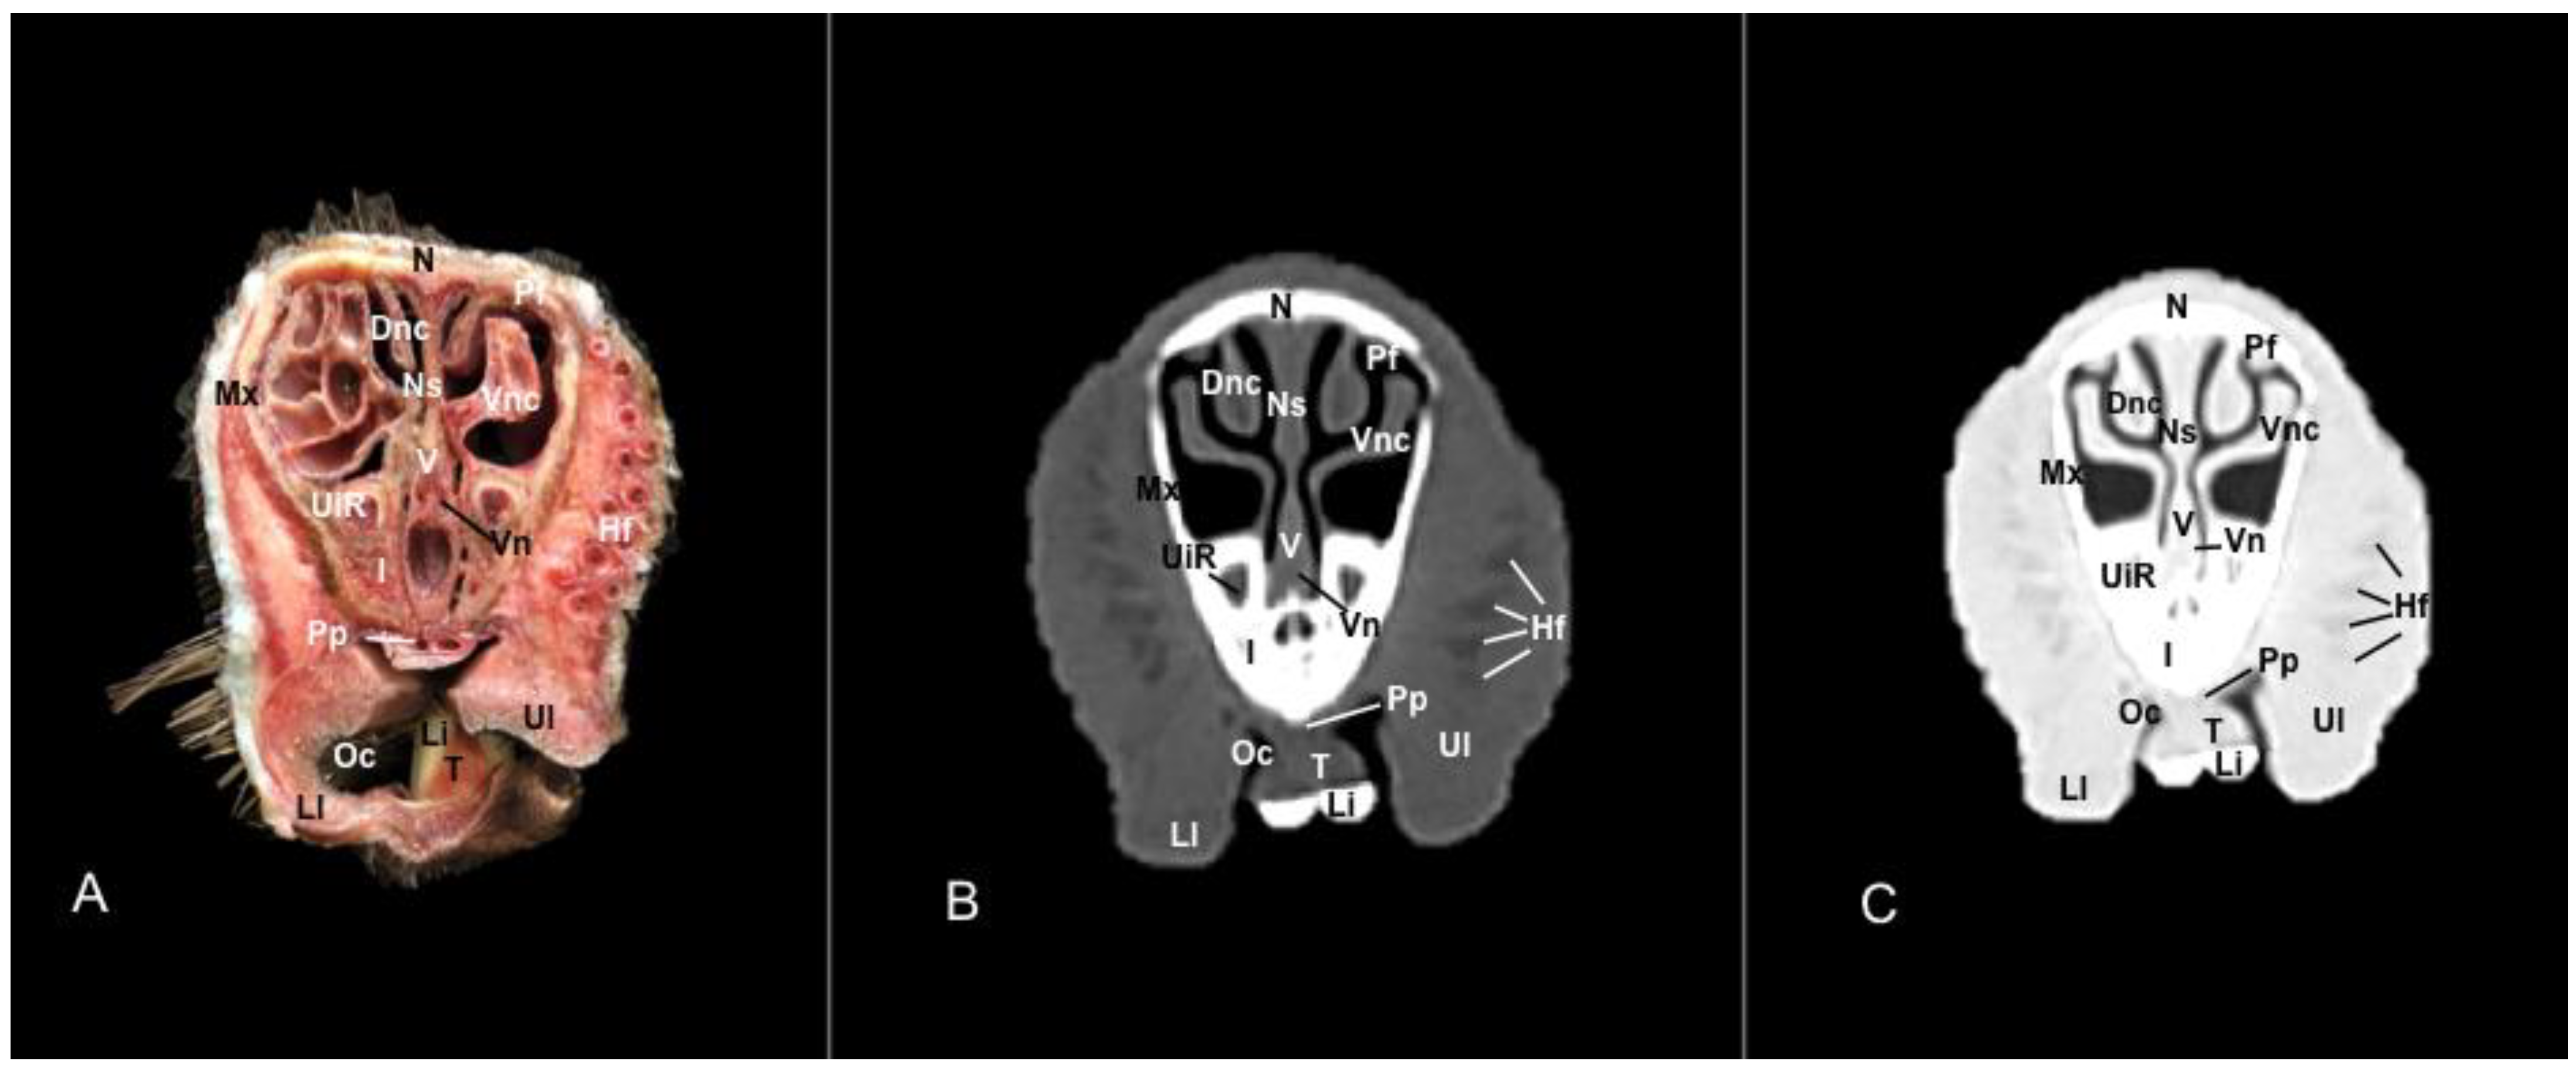

3.1. Anatomical Sections

3.2. Computed Tomography (CT)